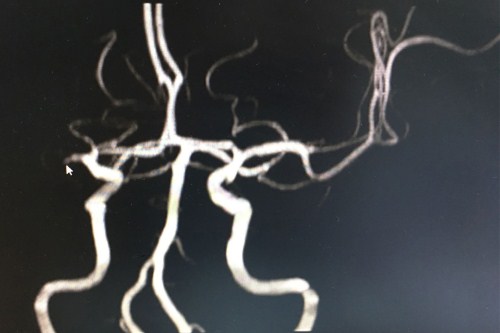

高血壓三級(jí)、冠心病、房顫、大面積腦梗死,左側(cè)偏癱、昏迷、肺部感染...愛(ài)人回到家,發(fā)現(xiàn)老姚昏倒在地,立馬叫車將他送到藍(lán)十字腦科醫(yī)院。住院后,在李振并主任(神經(jīng)內(nèi)科5病區(qū)主任)的安排下,立即檢查CT,右側(cè)大腦半球大面積低密度影,考慮大面積腦梗死。又做MRI(磁共振成像)和MRA(腦血管磁共振成像),提示右側(cè)大額顳葉,頂葉,枕葉大面積梗死,右側(cè)大腦中動(dòng)脈閉塞,病人處于昏迷狀態(tài),情況非常危急。

術(shù)前血管磁共振:右側(cè)額葉、顳葉及基底節(jié)區(qū)大片腦梗塞,腦動(dòng)脈硬化,右側(cè)大腦中動(dòng)脈閉塞(光標(biāo)指向處)